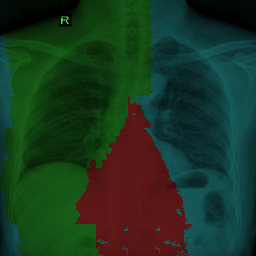

, where is the concatenate operation that concatenate along a new dimension. We have with and is a small number to ensure numeric stability, e.g. . Without prior information over the true label distributions, we setup as a constant vector, i.e. . Given , we transform a partially supervised problem into a fully supervised one and we can utilize any existing supervised segmentation network and loss function. See Fig. 3 for the illustration of the training pipeline. In each class channel of the vicinal label, the continuous probabilities are transformed into grayscale pixels for visualization. There are two origins of uncertainty for generating the vicinal labels when there is an overlap between partial labels. First, the sampling of input images is stochastic. Second, is randomly sampled from a Dirichlet distribution (e.g. used in Fig. 3). See the upper right corner in Fig. 3 for visual examples intuitively, where and have an overlapping region.

See Fig. 4 for the illustration of adversarial training with the vicinal examples. We denote VLUU with adversarial training as VLUU-ADV.